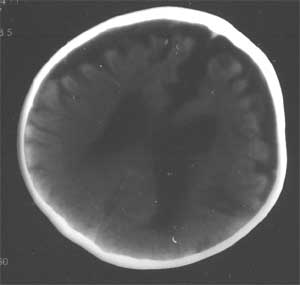

通过脑ct看医生说比较严重 ct检查报告是:右侧基底节区低密度灶,脑沟裂明显增宽,脑室系统清度扩大,中线结构无移位。 ct诊断:1。右侧基底节区缺血性改变 2。脑发育不良

幕上幕下脑室、脑池、脑沟均见扩张积液,考虑脑发育不良。片子质量不好,前囟门似乎偏小,颅骨骨缝不知是否有闭合。9个月幼儿,头围应该不小于40厘米,请测量头围周径。应该没有胼胝体发育不良。至于“右侧基底节区缺血性改变”,片子质量差,看不清楚。

从ct片看1大脑纵裂增宽2侧脑室扩大3蛛网膜下腔增宽 应考虑1胼胝体发育不良,2脑发育不良或萎缩(两周前一般无临床意义应称蛛网膜下腔增宽或外周性脑积水)

不同意胼胝体发育不良的诊断,现在ct表现为脑沟、脑池增宽,双测额骨内板下方带状液体影,双测侧脑室略扩大,我认为应诊断为1、脑发育不全。2、外部性脑积水。情况应该很严重。

2 患儿有外部性脑积水,但其实质是蛛网膜下腔的增宽,为自愈性,无需处理,一般前囟闭合后便自行消失。ct表现为大脑纵裂和双额颞区蛛网膜下腔增宽,可有轻度的脑室系统扩张。

3 本例 患儿除外部性脑积水外的确有其他部位脑沟的增宽,尤以双顶叶为著,右侧基底节区可见低密度灶,以上可以为新生儿缺氧缺血性脑病所遗留,但并不严重,我想随着治疗锻炼患儿恢复应该会不错的。[em1][em4][em9][em14]